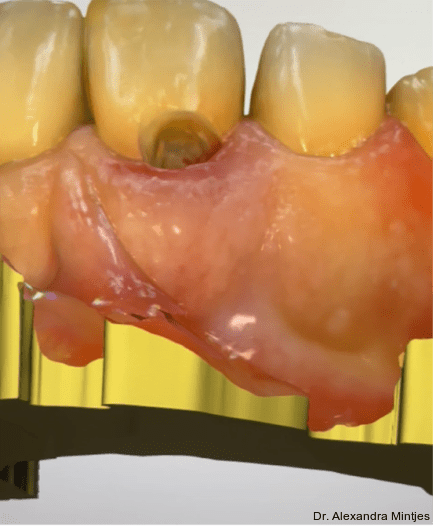

Die Behandlung erfolgte in mehreren präzisen aufeinander abgestimmten Schritten. Zunächst wurde die alte Kompositfüllung vollständig und atraumatisch entfernt, ohne eine Blutung der Schleimhaut zu provozieren. Nur durch das minimalinvasive und vorsichtige Vorgehen bei der Entfernung der insuffizienten Kompositfüllung konnte die Blutungsfreiheit erreicht und somit eine solide Grundlage für die folgenden Behandlungsschritte gewährleistet werden. Anschließend wurde die weiche Zahnhartsubstanz mithilfe eines Rosenbohrers sorgfältig exkaviert (Abb. 3). Überschüssige Guttapercha wurde ebenfalls abgetragen, um eine saubere und stabile Basis zu schaffen.

Die Sondierung ergab eine vertikale Defektausdehnung von etwa sechs Millimetern bei einer Taschensondierungstiefe von lediglich zwei Millimetern. Dies wies somit auf eine parodontale Gesundheit hin. Der gereinigte Defekt wurde anschließend mit einem lichthärtenden Flow-Komposit versiegelt, um Unebenheiten auszugleichen und die Adaptation der geplanten CEREC-­Keramikrestauration zu optimieren (Abb. 4).